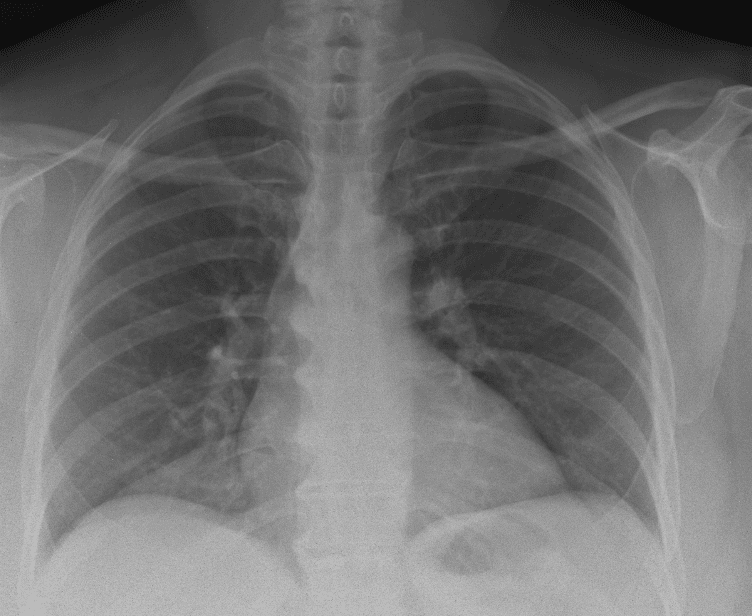

Practice Cases